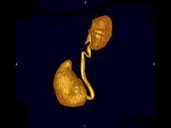

男,72岁,排尿困难1年余,无手术病史,CT扫描如图所示,下列说法正确的是?(?)

• A.一侧肾脏缺如

• B.膀胱的后上方可见一囊性肿物,该囊性肿物与膀胱相通

• C.考虑为先天性孤立肾

• D.该囊性肿物考虑为膀胱憩室

• E.该囊性肿物考虑为输尿管囊肿